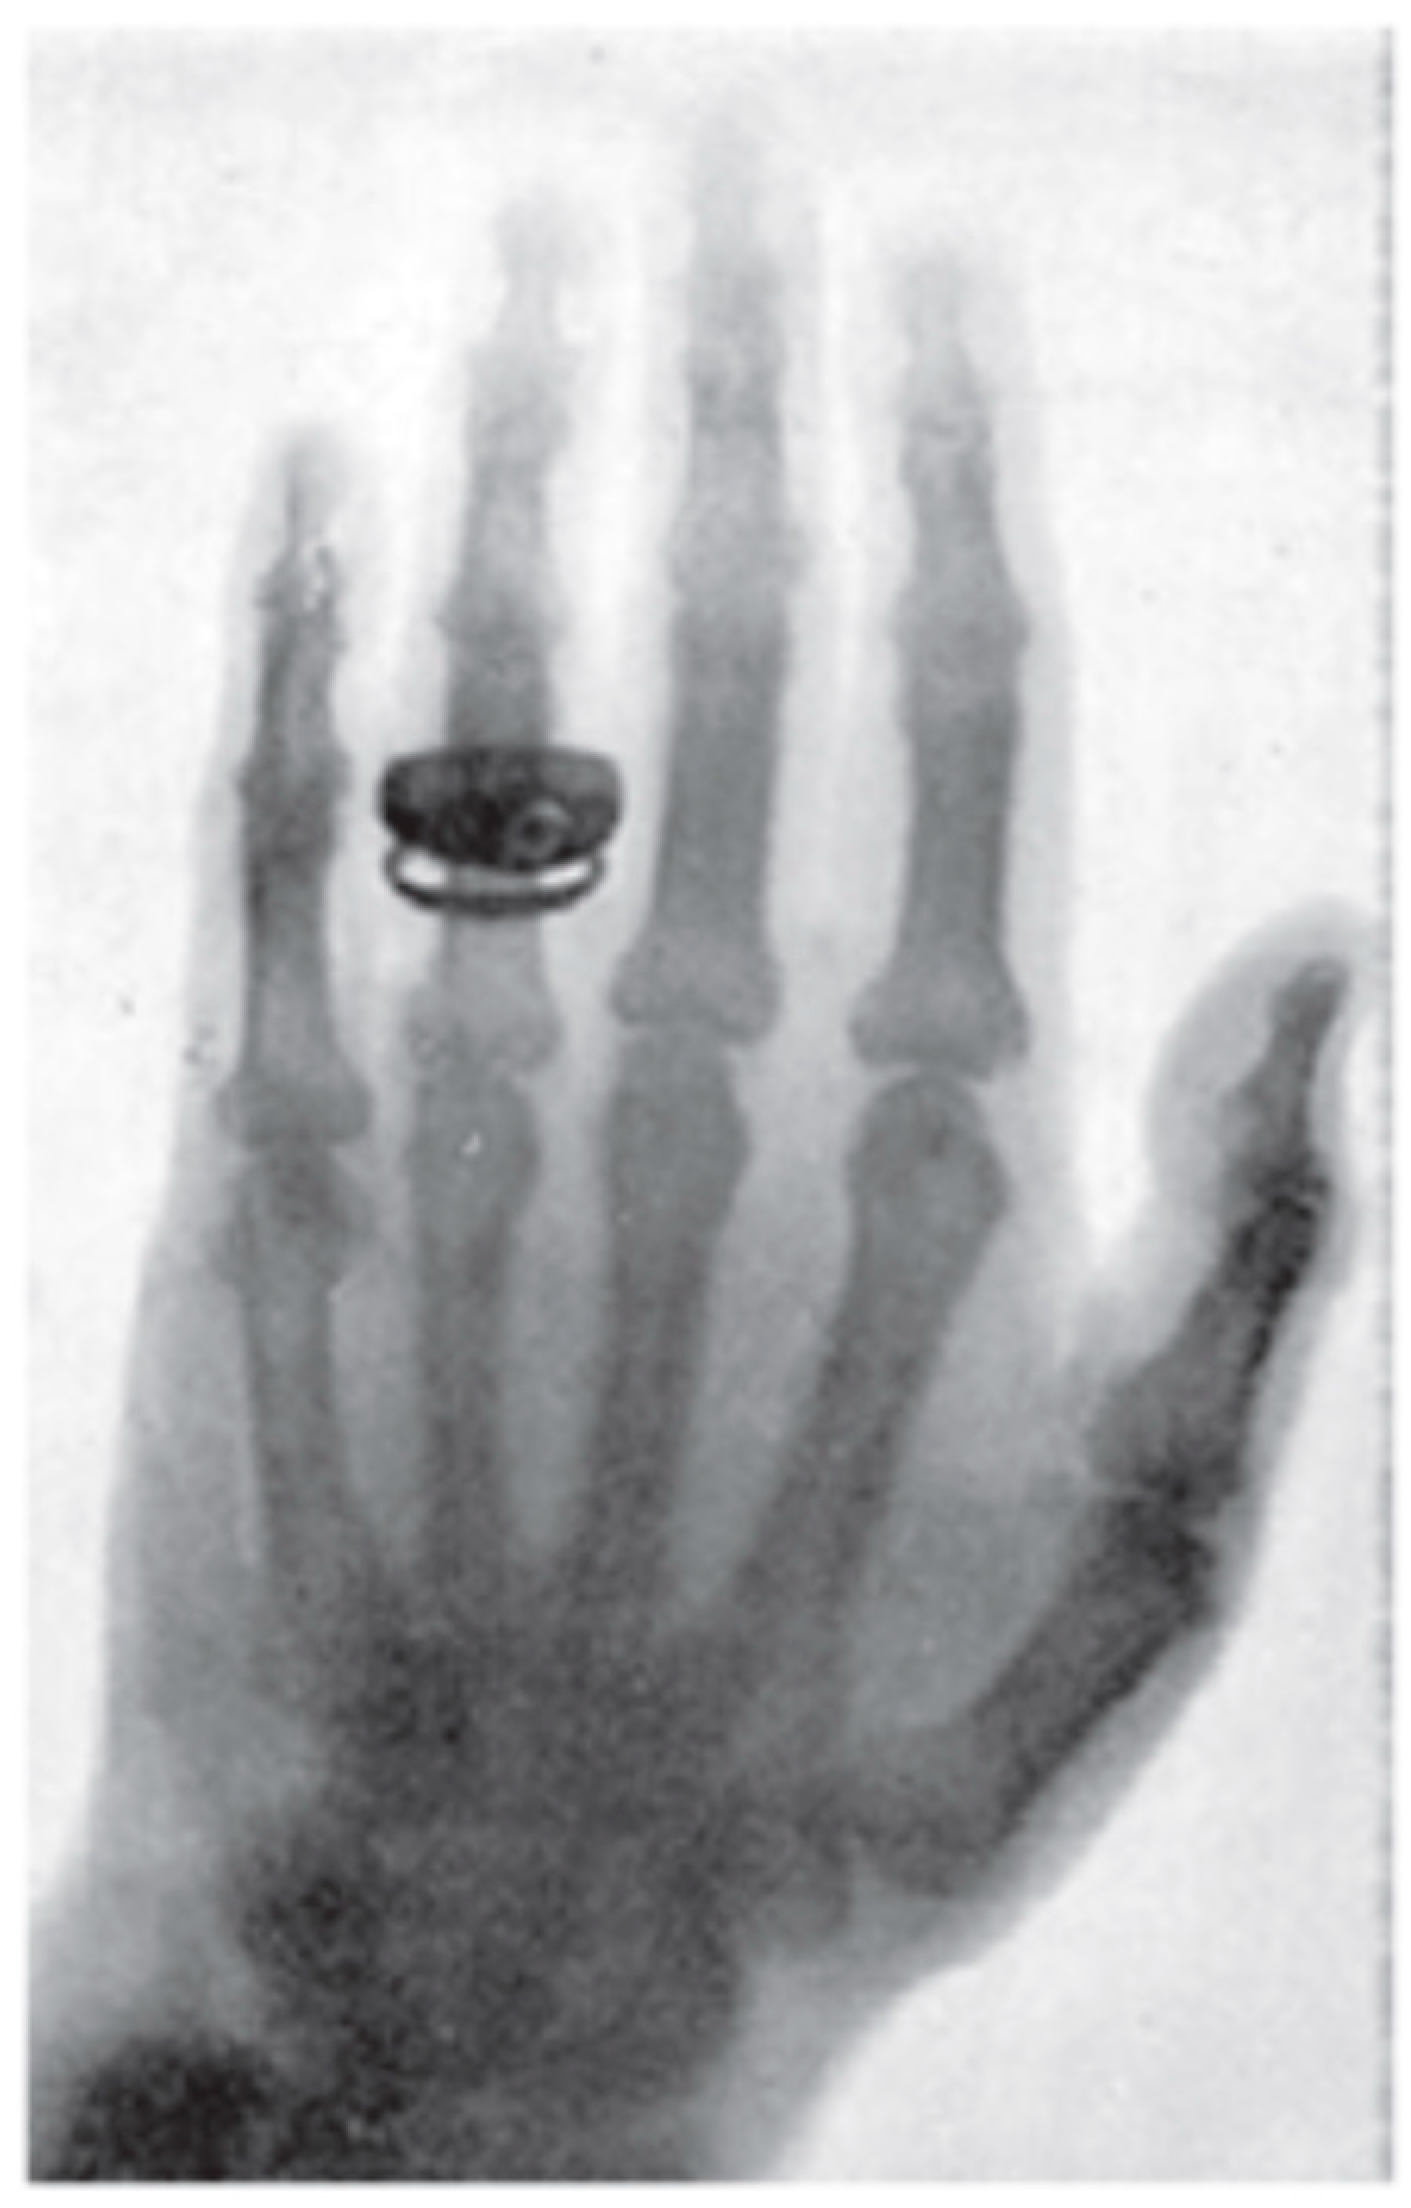

History of Engineering and Technology One of the first xray photos X Ray Images Invented By Mistake wilhelm conrad röntgen was 40 years old and a physics professor at the julius maximilian university of wurzburg. Edwin frost and his brother, dr. Despite the fact that the tube was. In 1895, a german physicist named wilhelm roentgen was working with a cathode ray tube. A year after roentgen’s discovery, in 1896, dr. on november 8, 1895,. X Ray Images Invented By Mistake.